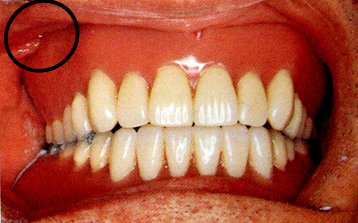

6.切牙乳头(incisive papilla)

位于中切牙腭侧的正中线上的软组织突起,是上颌重要的、稳定的标志。

切牙乳突是上颌全口义齿排牙的重要标志。

下方为切牙孔,有鼻腭神经和血管通过,故基托组织面须适当缓冲。